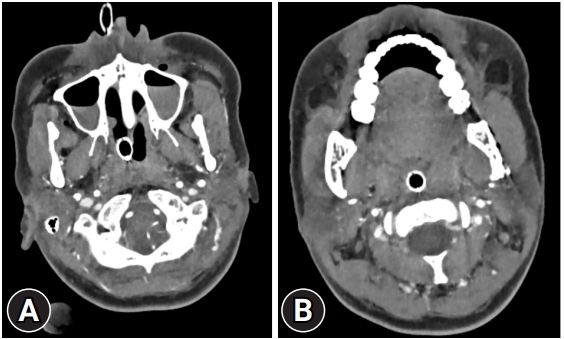

The nasotracheal tube (NTT) is frequently used in oral and maxillofacial surgery and is generally considered a safe means of protecting the airway while ensuring an adequate surgical field. The most common complication associated with NTT is epistaxis, and only a few cases of foreign body obstruction have been reported. In this case report, the authors aimed to highlight the potential for NTT obstruction following surgery. A 24-year-old female patient, who underwent mandibuloplasty and rhinoplasty at a local clinic, was referred to our hospital patient due to dyspnea and edema on her right mandibular angle. Even with NTT, patient continued to experience mild dyspnea and tachypnea, so a T-piece was applied. However, tachycardia accompanied by a sudden worsening of dyspnea was observed, and bag-valve-mask ventilation was initiated promptly. But oxygen saturation remained unimproved, so an emergency cricothyroidotomy was performed. After 4 hours, the patient's condition stabilized. Upon examination, the previously inserted NTT was identified, and a blood clot approximately 10 cm long at the NTT tip was discovered, causing lumen obstruction. The obstructions of NTT can lead to serious or life-threatening consequences if left unobserved or ignored. Therefore, when a patient with an NTT complains of dyspnea, clinicians should promptly investigate the possibility of partial NTT obstruction to ensure the airway's security.